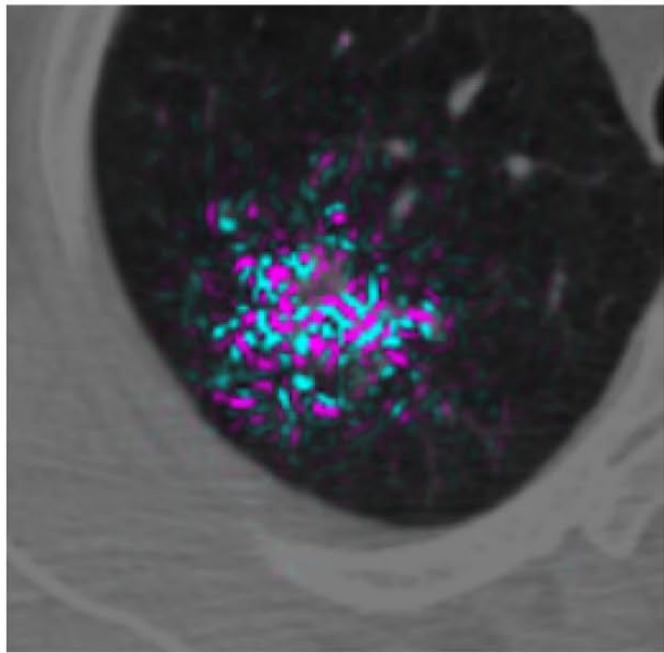

Another 2019 study (Ardila et al), a collaboration between Google's Deep Mind and Northwestern University, reported promising results for better detecting small tumors in CT. The researchers created a three-dimensional AI model that was able to take into account regions of concern within the lung. Making use of both current scans and those from before receiving a lung cancer diagnosis, the model showed good accuracy (94%) in detecting cancerous nodules; outperforming six radiologist reviewers while also reducing the number of false positives and false negatives.

The model's ability to analyze a volume, rather than "merely" a sequence of two-dimensional slices appears to have provided a benefit. The context of the additional pixels allowed the model to inspect patterns in blood vessels and other connective tissue not part of the tumor. This caused the model to highlight contributing factors not directly part of the growth, but capable of providing insight into its development and better predictive accuracy.